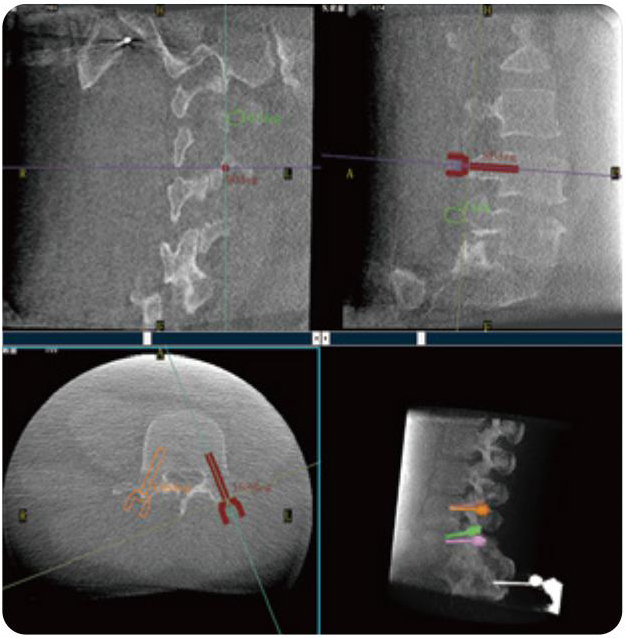

PL300B可应用于多节段脊柱外科手术,辅助医生定位病灶部位,为脊柱外科手术(经皮椎体成形术、椎弓根螺钉内固定术等术式)提供术前手术流程规划、入钉位置、角度可视化引导,模拟仿真入钉辅助。

PL300B搭配糖心vlog 自主研发生产的平板3D C形臂,借助一体化自适应配准( 轨迹配准)技术,通过追踪C形臂三维采集轨迹,自动完成图像坐标建立和系统坐标配准。配准精度更高,操作步骤少,系统运作效率高。